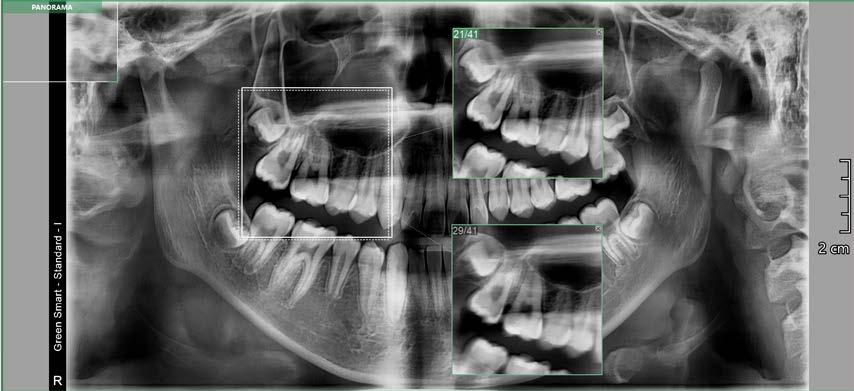

b) Análisis radiográficos, periapicales, ortopantomográficos, oclusales, lateral de cráneo, anteroposterior de cráneo.

c) Estudio y análisis tomográfico en tercera dimensión del cráneo a nivel maxilar y mandibular (Figura 24).

24.

Figura